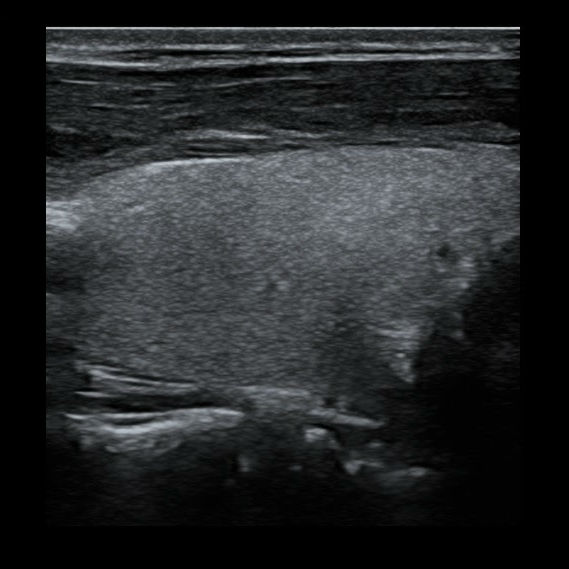

Нажав кнопку iScape мы просто проводим датчик вдоль оси сканирования, и прибор сопоставляет сканируемые изображения в единую, практически бесконечно длинную картину. Теперь влезет всё и продольное сечение щитовидной железы, и широкие гематомы, и крупные кисты Бейкера, и ахиллово сухожилие во всю длину с подробным указанием точек надрыва и указанием расстояния от пяточной кости для уточнения топики травмы даже при изгибе контактной поверхности.